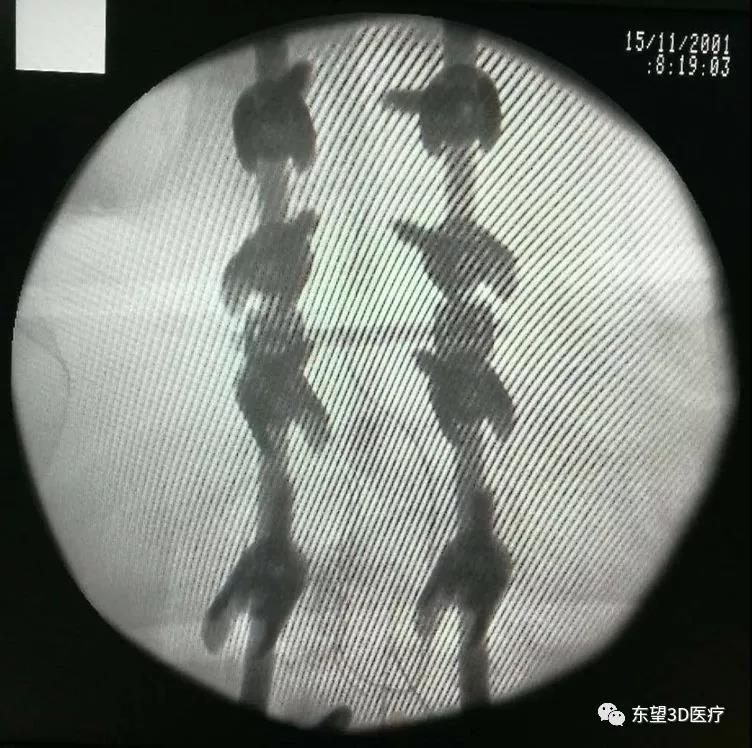

術中置釘、減壓見硬膜囊脊髓搏動良好

\

X線透視椎弓根釘位置準確

透視見畸形矯正滿意,縫合切口